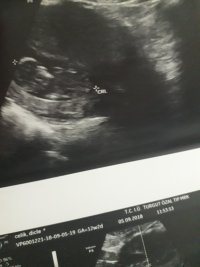

Dun malatyada verildi 12 +4 gunluk lutfen yorumlayin

nub çıkıntısının üzerinde imleç var cinsiyet anlaşılmıyor ilk sayfayı incelemenizi öneriyorum görselin kalitesi konu içinde yer alan görselle aynı olmalıdır.

Görsellerde nub çıkıntısı belli değil . Ultrasonu yapan doktor cinsiyeti hakkında bilgi vermiştir mutlaka ama şunu belirtmeden geçmeyeyim. Bu haftalarda cinsiyet tahmininde yanılma payı çok yüksek 17-19 ve 20 ci haftalarda bebeğin cinsiyetini net olarak öğrenebilirsiniz.